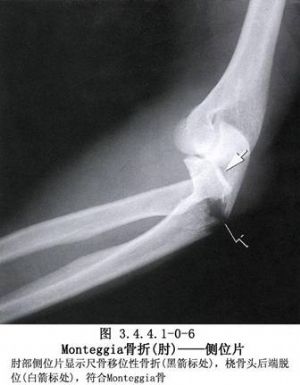

尺桡骨干骨折常见。由于暴力的原因和受伤瞬间肢体的姿式以及肌肉收缩的状态不同,可以发生尺桡骨干双骨折或单骨折。其中,又可发生于不同平面。尺骨干上1/3骨折合并桡骨小头脱位(孟氏骨折Montaggia fracture)。桡骨干下1/3骨折合并下尺桡关节脱位(盖氏骨折Galeazzi fracture)。其中尺桡骨干双骨折占全身骨折的5.41%,为第3位。桡骨骨折占4.23%,为第5位。尺骨骨折占1.05%,为第17位。孟氏骨折占0.63%,为第38位。盖氏骨折占0.35%,为第50位。由于前臂具有旋转功能,一旦发生骨折,除重叠和侧方移位外,尚有严重的旋转移位。因此,对复位的要求较高。如手法复位不满意,难以达到预期功能的恢复,即有手术复位的指征。相关解剖及影像表现见下图(图3.4.6.1-0-1~3.4.6.1-0-6)。